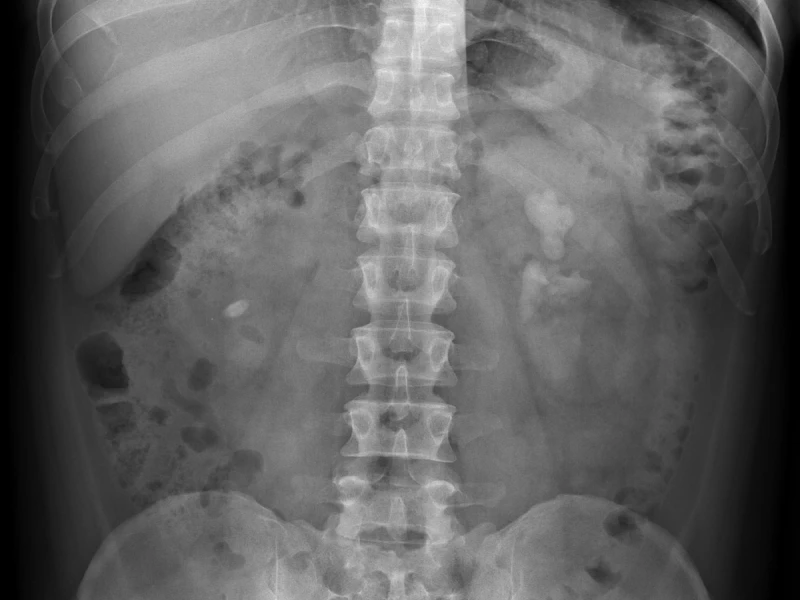

Radiografía de abdomen